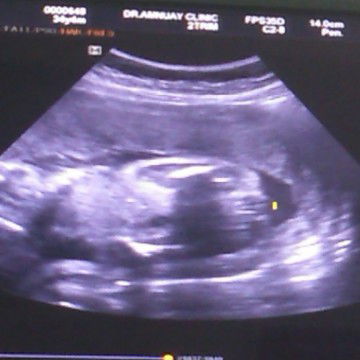

อัลตร้าซาวด์ตอน24weekคุณหมอบอกว่าผู้หญิง แต่แอบกังวลว่าออกมาจะเป็นผู้ชายไหม#ขอบคุณสำหรับคำตอบค่ะ

น่าจะเป็นผญ.ค่ะแม่

น่าจะผู้หญิงนะคะ

น่าจะหญิงนะคะ